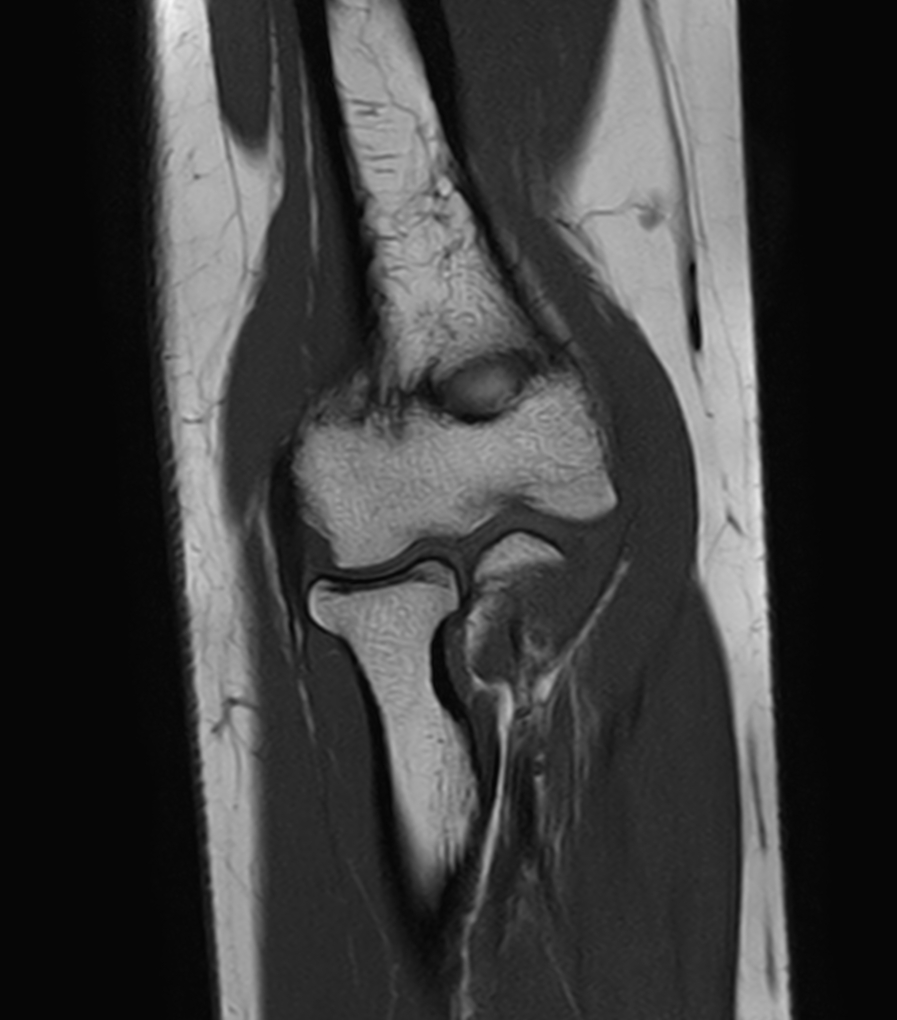

Coronal T1w TSE

Coronal PDw SPAIR